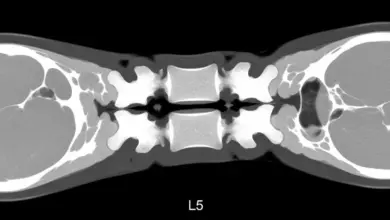

Espondilólise: causas, sintomas e tratamento

A espondilólise é uma causa frequente de dor lombar em adolescentes e adultos ativos. O problema atinge a pars interarticularis…

Abaulamento discal difuso L5 S1: sintomas e tratamento

O abaulamento discal difuso L5 S1 aparece com frequência nos laudos de ressonância, gera dúvidas e nem sempre está ligado…